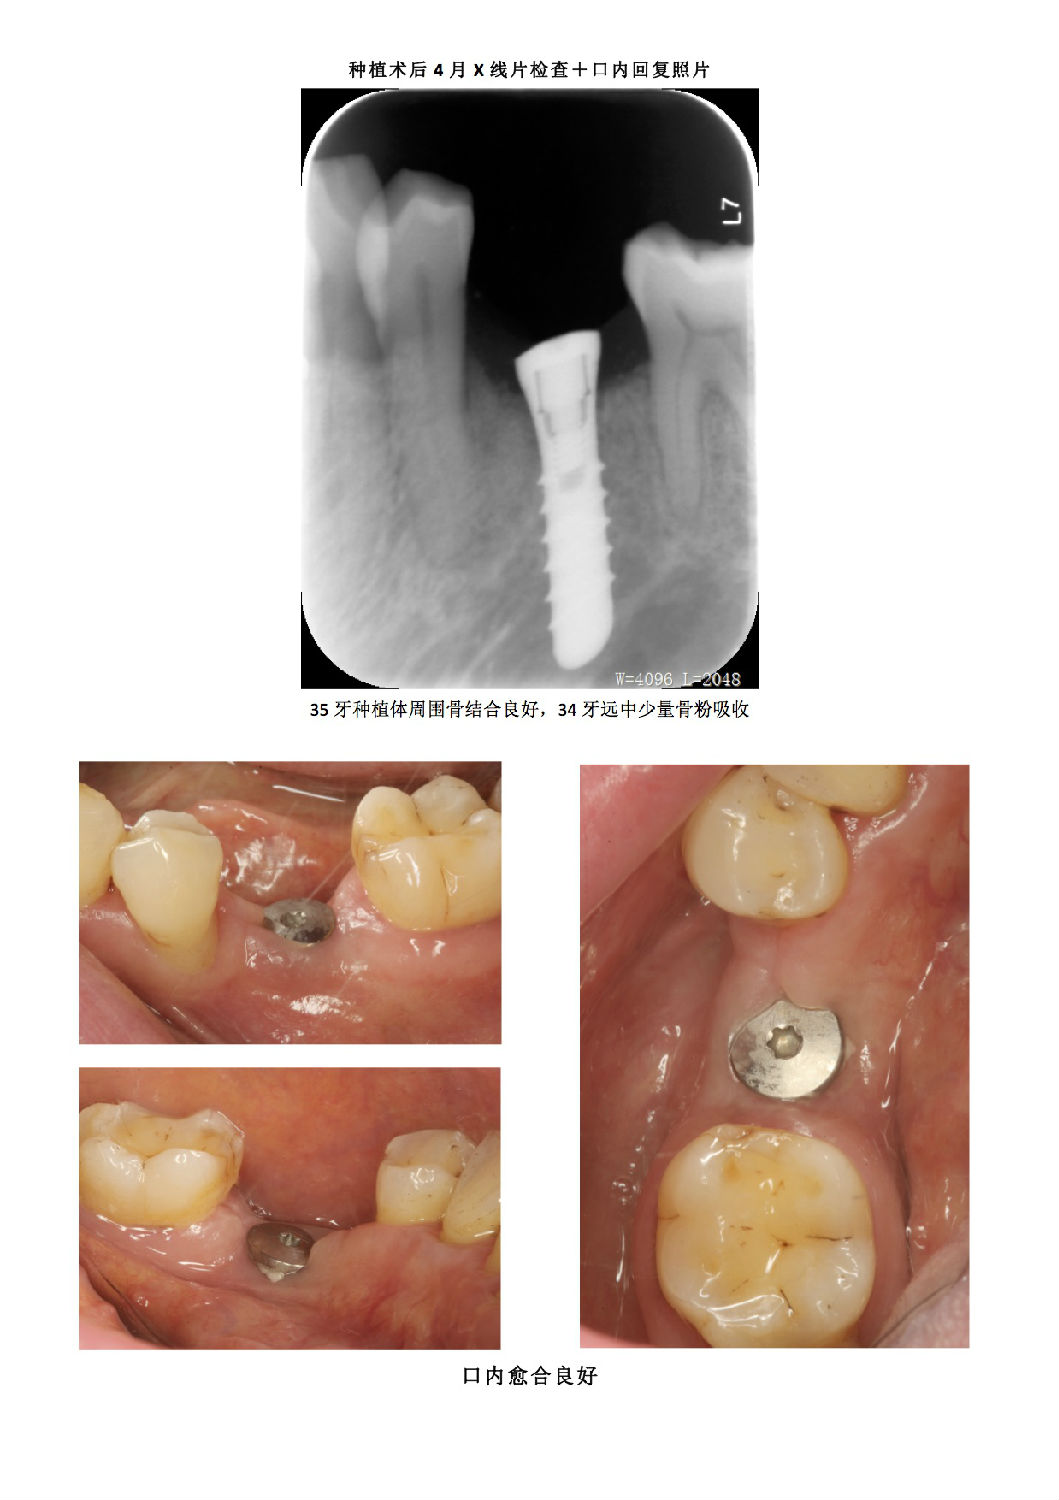

牙周病患者種植治療+鄰牙GTR病例匯報